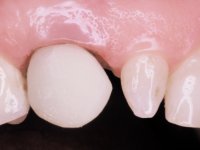

Paciente do sexo feminino, com 47 anos não fumadora. Apresentou-se na consulta com o dente 1.3 com tratamento endodôntico e com um espigão falso coto fundido, reabilitado com uma coroa provisória. Os dois incisivos laterais superiores são conoides e de reduzida dimensão. O dente 2.2 apresenta mobilidade, consentânea com uma significativa reabsorção óssea entre o dente 2.1 e o dente 2.3 Os dois incisivos centrais estão separados por um diastema de 3mm e o dente 2.3 apresenta uma oclusão cruzada com o dente antagonista. Verifica-se também a ausência de alguns dentes posteriores e uma higiene oral razoável. Na segunda intervenção realizada passados 8 anos, verificou-se que os incisivos centrais superiores se apresentavam cromaticamente mais escuros e apresentavam um sulco longitudinal no esmalte que estando pigmentado comprometia esteticamente o sorriso. O trabalho realizado na primeira fase do tratamento mostrava-se competente estética e funcionalmente. Por fim, um ano após a última intervenção, a paciente apresentou-se com uma fratura da faceta colocada no dente 2.1 provavelmente em resultado de estar em contacto com o coto do implante. A rigidez da anquilose implantar, pode ter sido a causa desta fratura. Outros casos deste tipo de fratura já foram observados por mim em situações clínicas idênticas. A faceta do dente 1.2 apresentava-se esteticamente comprometida e a própria estrutura dentária apresentava uma pequena cárie e, pelo que se recomendaria a sua substituição.

O tratamento iniciou-se com a re -preparação do coto do espigão falso coto fundido, com o objetivo de colocar as linhas de acabamento cervical com uma localização intra-sulcular e simultaneamente confecionar uma coroa provisória adaptada. Com um tratamento ortodôntico muito simples, fechou-se o diastema entre os incisivos centrais superiores e estabilizou-se esta posição com um arame colocado na superfície palatina dos centrais, funcionando como contenção. Posteriormente procurou-se fazer uma tração ortodôntica lenta do dente 2.2 com o intuito de diminuir, ainda que muito ligeiramente a perda óssea vertical nessa zona. Finalizada a tração, foi feita a extração do dente 2.2 e a zona foi reabilitada provisoriamente com uma coroa de resina composta colada aos dentes adjacentes. Foi colocado um implante dentário na zona do dente 2.2 sendo novamente colada a coroa provisória em resina, reabilitando provisoriamente a paciente durante o período de osseointegração. No dente 1.3 foi feita uma gengivectomia com bisturi elétrico, com a intenção de subir o nível cervical do 1.3 conseguindo uma maior harmonia com o dente 2.3. Estabilizados os tecidos moles, foi feita uma impressão com a técnica de moldeira aberta, utilizando silicones de adição de consistência “putty” e “light”. A recolha da cor, tanto da componente dentária como dos tecidos moles foi feita pelo ceramista no consultório.  No laboratório as impressões foram passadas a gesso e deram origem a modelos de trabalho que foram devidamente analisados. Foi decidido confecionar um “abutment” metalo-cerâmico aparafusado sobre o implante. Este “abutment” foi fundido com uma liga nobre e posteriormente revestido a cerâmica coronária e gengival. Dada a inclinação do implante o aparafusamento condicionou de forma inevitável a saída do orifício do parafuso pela superfície vestibular. No sentido de esconder esta situação, o desenho do “abutment” já foi idealizado com a intenção de acomodar na superfície vestibular a colagem de uma faceta feldspática. Este “abutment” foi provado em boca e foram feitos ajustes no componente cerâmico gengival. A sua adaptação aos tecidos moles foi feita tanto de forma subtrativa, com broca, como de forma aditiva, acrescentando resina composta de tonalidade gengival. Este acrescento de resina seria orientador do ceramista na colocação final da cerâmica de tonalidade gengival. A coroa que reabilitaria o dente 1.3 foi cimentada nesta consulta de prova com cimento de ionómero de vidro reforçado com resina composta. Finalizado o trabalho em laboratório da faceta sobre o 1.2 e o “abutment” e a faceta para o implante este foi colado em boca, após a colocação do isolamento absoluto. O trabalho satisfez plenamente a paciente. Durante oito anos a paciente foi seguida regularmente, mostrando-se agradada com o tratamento efetuado, no entanto começou a mostrar interesse em intervir esteticamente nos incisivos centrais superiores. Decidida a segunda fase da nossa intervenção, foi feita a preparação dentária dos dentes 1.1 e 2.1 para a colocação de duas facetas feldspáticas. Particular cuidado foi tido na preparação inter-proximal distal junto ao “abutment” do implante. Foi preciso avaliar muito pormenorizadamente o eixo de inserção da faceta em relação ao “abutment”. As facetas feldspáticas foram confecionadas em laboratório e posteriormente coladas em boca após a colocação de isolamento absoluto. Um ano após, iniciamos a nossa terceira fase de tratamento, após a faceta colada no dente 2.1 ter fraturado. A preparação dentária foi feita sobre a faceta colada, procurando estender mais para palatino o interface inter-proximal distal. O objetivo seria passar para mais palatino do ponto de contacto o interface faceta-dente. O preparo dentário do dente 1.2 também foi muito reduzido, limitando-se a criar um eixo de inserção. Após confecionadas a coroa total e a faceta em laboratório foram coladas em boca. Primeiro foi colada a coroa utilizando-se um isolamento relativo com teflon, posteriormente foi colada a faceta após a colocação do isolamento absoluto. Na coroa utilizei este tipo de isolamento para evitar a utilização de grampos. Seria difícil de aplicar pela forma e dimensão do dente e agressivo para os tecidos moles. Após a colagem foi avaliada a integração oclusal do trabalho.